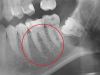

dv- Опубликовано 5 декабря, 2012 Автор Поделиться Опубликовано 5 декабря, 2012 (изменено) Зуб не пульпирован. Снимог годовалой давности. Изменено 5 декабря, 2012 пользователем dv- Ссылка на комментарий

shishok Опубликовано 5 декабря, 2012 Поделиться Опубликовано 5 декабря, 2012 Это свищевой ход.Вероятнее всего в шестом зубе умер нерв,воспаление из канала перешло на верхушку корня.К стоматологу-обязательно(необходимо перелечить каналы).На старом снимке пломба очень близко расположена к пульпарной камере(глубокий кариес).Снимок потребуется "свежий". Ссылка на комментарий

dv- Опубликовано 22 декабря, 2012 Автор Поделиться Опубликовано 22 декабря, 2012 Сходил к врачу (10 дней назад). Ничего не обнаружили, кость твердая в области где было это образование, сделали снимки (могу приложить), там тоже ничего нет. Боле-подвижности зуба тоже нет.Я так понимаю, что была какая-либо травма десны. Ссылка на комментарий

shishok Опубликовано 23 декабря, 2012 Поделиться Опубликовано 23 декабря, 2012 Cнимки всё равно неплохо бы посмотреть. Ссылка на комментарий